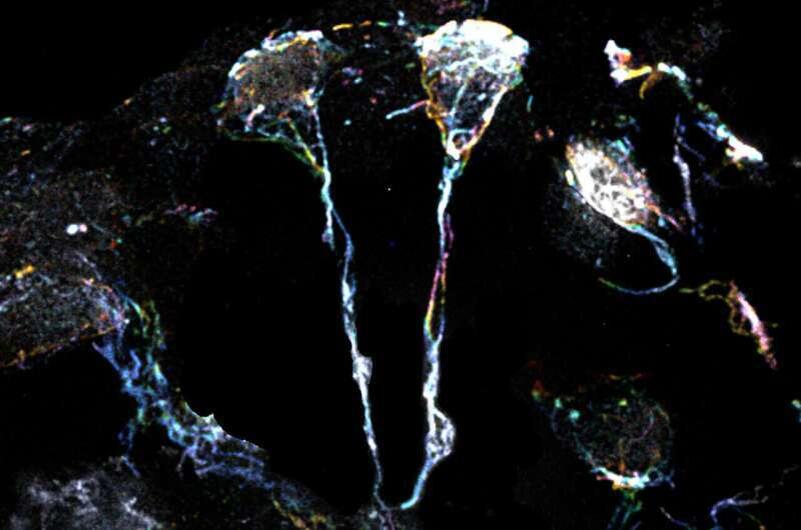

Ученые из Duke-NUS Medical School обнаружили важный механизм, который может изменить подходы к лечению неврологических заболеваний. Они выяснили, как определенные белки, вырабатываемые астроцитами, активируют спящие нейронные стволовые клетки. В ходе исследования ученые обнаружили, что астроциты выделяют белок Folded gastrulation (Fog), который запускает цепную реакцию, активируя путь белка Formin. Этот процесс приводит к активации актиновых волокон в клетках, что, в свою очередь, пробуждает нейронные стволовые клетки из их спящего состояния. Эти клетки начинают делиться и образовывать новые нейроны, способствуя восстановлению и развитию мозга. Ученые отметили, что это открытие добавляет новые знания о механизмах активации нейронных стволовых клеток и открывает возможности для разработки новых терапий. Понимание того, как этот сигнальный путь влияет на клетки, может помочь в лечении неврологических расстройств и старения мозга.